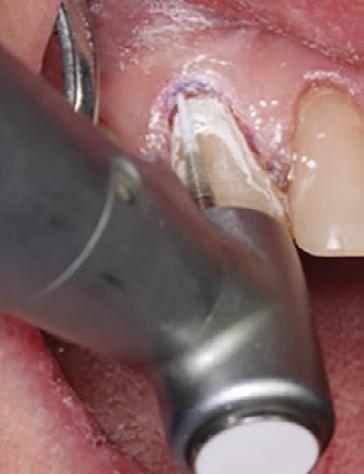

A fine-grit diamond bur was used to shape and finish the restoration (Fig. 9). Final luster was achieved using a twostep polishing system from Meisinger USA (Fig. 10). The retraction cord was removed at the end of the procedure.

Figure 9. Initial contouring and shaping of the restoration using a fine-grit diamond bur.